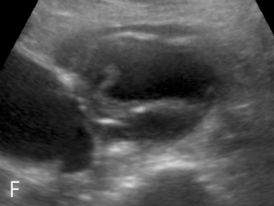

(F, G) Abdominal ultrasound transverse and longitudinal view demonstrated the aortic dissection and guide the fenestration.